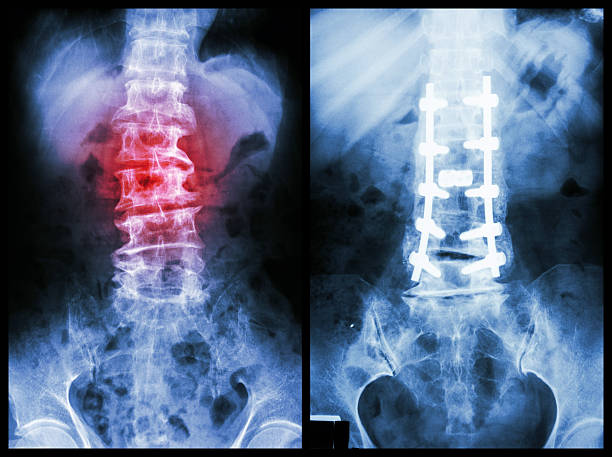

The kind and extent of the fracture determine the course of treatment. While complicated fractures frequently necessitate surgical intervention, minor fractures may heal with immobilization using plaster casts or splints. The Best Fracture Fixation Surgery in Bhiwandi uses state-of-the-art orthopedic techniques like internal fixation using plates, screws, or rods to support the fractured bone and promote faster healing. Following surgery, physiotherapy ensures optimal mobility and functional recovery.

Imaging tests such as X-rays, CT scans, or MRIs are carried out to determine the exact location and type of break following a comprehensive clinical examination.Orthopedic specialists performing the Best Fracture Fixation Surgery in Bhiwandi use these diagnostic tools to develop precise and customized treatment plans.A precise diagnosis is necessary for effective bone repair and long-term joint stability.